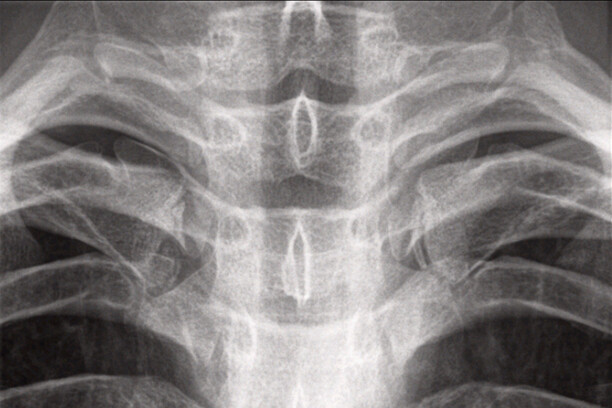

Sinds 1999 kunnen vreemdelingen zonder geldige identiteitsdocumentatie onderworpen worden aan een zogenaamd leeftijdsonderzoek…